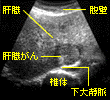

がん組織の影響で、体内の臓器や組織の形は変化する。この変化を画像に映し出してがんの診断に役立てるのが画像診断。X線や内視鏡を用いる診断のほか、CT検査(コンピューター断層撮影)、超音波診断法(エコー検査)、MRI検査(磁気共鳴映像)、血管造影法など、さまざまな方法がある。